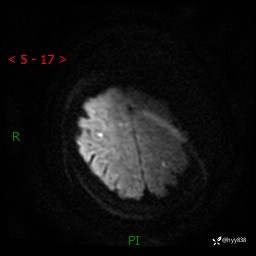

患者性别:女

患者年龄:57岁

简要病史:昏迷入院

临床诊断:昏迷

颅脑MRI(T2WI+DWI)